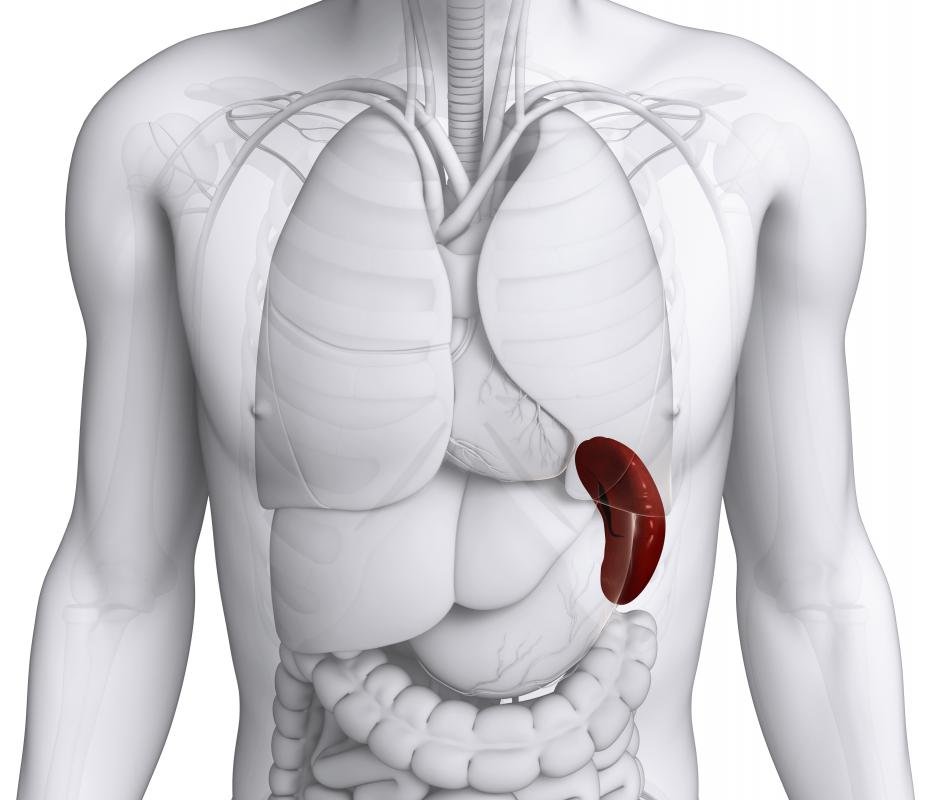

Accessory spleens are intriguing anatomical structures that can add an unexpected twist to our understanding of the human body. These small spleens, which can exist in addition to the main spleen, often go unnoticed but can play significant roles in our immune system and overall health. As we delve deeper into the world of accessory spleens, we uncover their functions, implications, and why they deserve more attention in medical discussions.

From their definition and physiological significance to their impact on individuals’ health, accessory spleens are more than mere anatomical curiosities. They can influence various medical conditions, and understanding them can improve diagnosis and management of related health issues. Let’s explore the fascinating world of these supplementary organs and their relevance in the medical field.

What exactly is an accessory spleen?

An accessory spleen is a small, additional spleen that can develop in the body alongside the main spleen, usually located near the primary organ.

How common are accessory spleens?

Accessory spleens are relatively common, occurring in about 10% of the population, though many people may not realize they have them.

Do accessory spleens have any functions?

Yes, accessory spleens can help with immune response and blood filtration, similar to the main spleen, contributing to the overall function of the lymphatic system.

Can accessory spleens cause health issues?

While accessory spleens are usually harmless, they can sometimes be involved in certain medical conditions, such as splenic torsion or in cases where surgical removal of the main spleen occurs.

How are accessory spleens diagnosed?

Accessory spleens are often discovered incidentally during imaging studies, such as ultrasounds or CT scans, performed for other reasons.